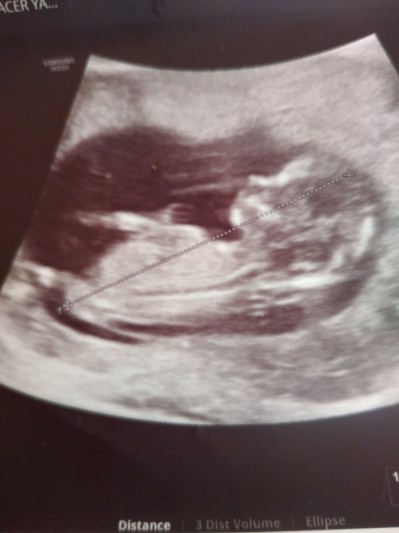

tecrübeli güzel anneler 12 haftalık ultrason görüntüsü, tahmini olan var mı :)